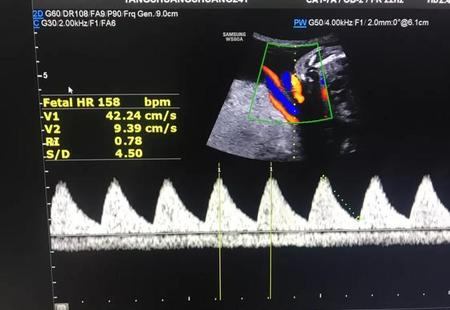

正常胎心率为120~160次/分钟。胎心率一般在安全范围内浮动,不是固定不变的值。我们在检查报告上看到的胎心率的值只是胎儿某一时刻的胎心率值。

胎儿的胎心率受到很多因素的影响。受胎动、宫缩、触摸及外界声响等方面因素影响,当然一般这些变化属于一过性变化。正是因为这些原因,胎儿的胎心率可能在检查时睡觉就低一些,在胎动时就高一些,所以用胎心来估计是男是女完全不科学,也没有事实依据。